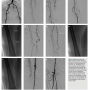

progressive claudication. He was started on a trial of medical therapy, including smoking cessation, cilostazol, and a walking program. The patient continued to smoke and despite medical therapy, complained of lifestyle-limiting claudication. He underwent diagnostic angiography and was found to have high-grade stenosis of the right SFA and complete occlusion of the left SFA (Figures 1A and 1B), and two-vessel run-off with an occluded anterior tibial artery. He was referred for percutaneous revascularization of the left SFA.

The right common femoral artery was accessed using a 4 French (Fr) micropuncture kit (Cook Medical).The sheath was upsized to a 5 Fr Avanti sheath (Cordis Corporation); using a 5 Fr IMA catheter (Boston Scientific) and an exchange-length Glidewire (Terumo Corporation), the catheter was advanced into the left common femoral. The sheath was then upsized to a 6 Fr, 45 cm Pinnacle Destination sheath (Terumo Corporation) placed in the origin of the left SFA. After administration of heparin, an Asahi Miracle Bros 6 wire (Abbott) was advanced to the cap. A Wildcat catheter (Avinger) was then advanced over the wire distally. An attempt to engage the cap resulted in deflection of the Wildcat into the collateral. Several attempts were made using the back end of the wire advanced to the distal tip of the catheter to provide more support while utilizing the Wildcat in different modes. Repeated attempts resulted in advancement of the device into the collateral branch. Next, an angled 0.18˝ QuickCross Extreme (Spectranetics) was used with a Treasure 12 guidewire (Abbott). Multiple attempts were made to advance the Treasure 12 wire into the proximal cap. It was felt this might allow advancement of the Wildcat to the cap without concern of deflecting into the collateral. Unfortunately, the proximal cap could not be penetrated secondary to the calcium as well as the angle and presence of a collateral. At this point, consideration was given to using an angled Glidewire and QuickCross catheter, and attempt a subintimal approach or bring the patient back for popliteal access. After further examination of the angiograms and angulated views (ipsilateral 20°), it was felt that there was an adequate collateral to attempt transcollateral passage of a wire. The Destination sheath was withdrawn into the left common femoral, and the wire was advanced into the collateral utilizing a Runthrough wire (Terumo) and a Finecross catheter (Terumo). Due to poor visualization of the catheter, the Finecross was exchanged for a 0.14˝ QuickCross and the wire was exchanged for a 300 cm Asahi Fielder wire (Abbott). Selective injection was then performed of the collateral through the QuickCross (Figure 1C). The Fielder wire was negotiated through the collateral and into the distal lumen of the SFA (Figure 1D). The 0.14˝ QuickCross was then advanced into the SFA in a retrograde manner and the wire was changed to an Asahi Confienza wire (Abbott). The wire was advanced in a retrograde manner through the calcified lesion to the proximal cap (Figure 1E). The cap could not be penetrated, despite attempts with several wires (Confienza, Cross-It, Pilot 300). At this time, the 0.14˝ QuickCross was exchanged for an 0.18˝ QuickCross through the collateral in a retrograde manner. The wire was then changed to a Treasure 12 wire, which easily penetrated the cap. The wire was then advanced into the left common femoral artery and exchanged for a Runthrough wire. Several attempts were made to rewire the sheath or rewire an angled catheter. This was in order to externalize the wire and proceed with revascularization. These attempts were unsuccessful. Multiple attempts were made to snare the wire by utilizing a 2.0 mm loop snare (eV3). This also was unsuccessful. At this point a 2.0 x 100 Coyote balloon (Boston Scientific) was advanced via the collateral into the lesion in a retrograde manner. The vessel was dilated at 6 atm for 20 seconds (Figure 1F). At this point, a Fielder wire was easily advanced in an antegrade manner into the tibioperoneal vessel and then exchanged for a RunThrough wire (Figure 1G). A 2.0 TurboElite Laser fiber (Spectranetics) was then utilized to debulk and modify the plaque as well as facilitate balloon delivery (Figure 1H). The lesion was

predilated with a 6.0 x 100 AngioSculpt scoring balloon (AngioScore) at 4 atm x 2 minutes (Figure 1I). This was performed in an overlapping manner. This was then followed by placement of a 7.0 x 150 SMART stent (Cordis), which was postdilated with a 7.0 x 100 Sterling balloon (Boston Scientific) at 4 atm (Figure 1J). Final angiography demonstrated brisk flow without embolization, perforation, or dissection. The sheath was withdrawn and a Mynx closure (AccessClosure) was performed in the right groin. The patient was discharged home the following morning without incidence.